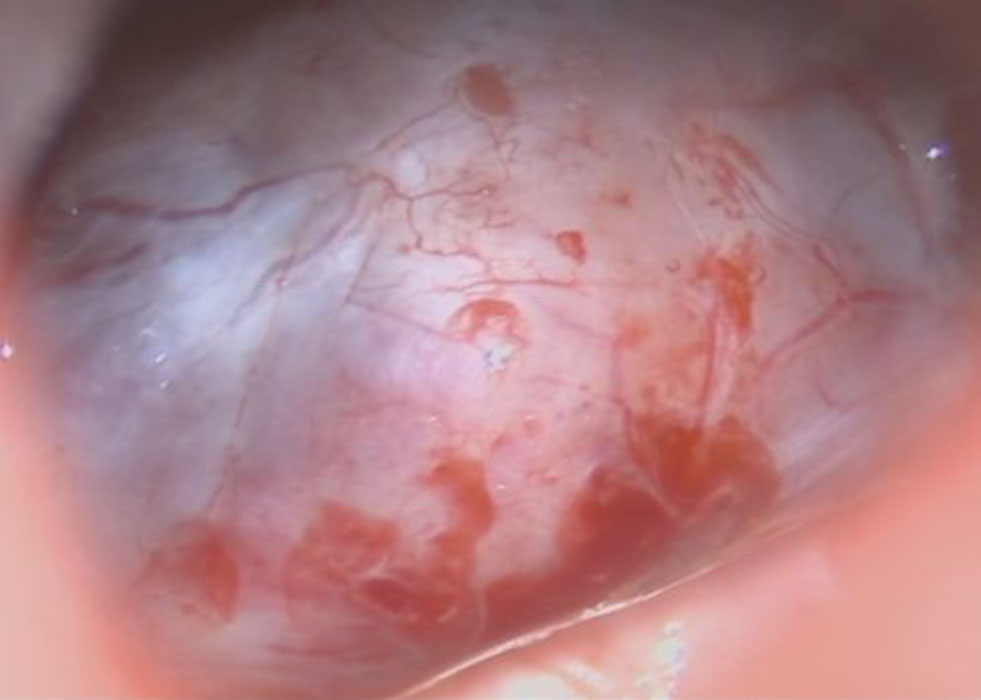

手術前1

手術前2

術中写真

摘出 前

摘出 中

摘出 後